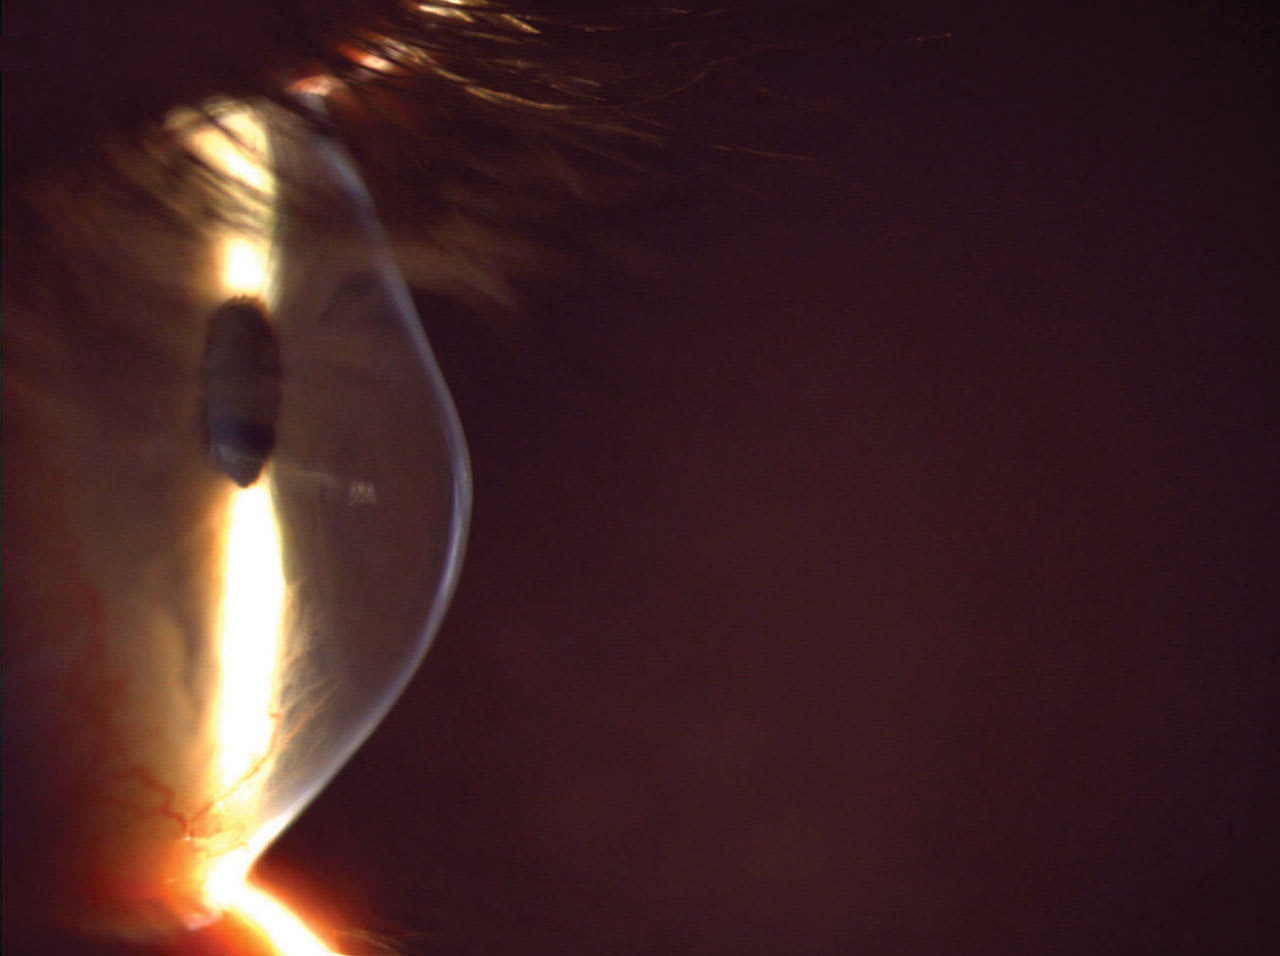

MANY PATIENTS who have moderate to advanced progressive keratoconus (Figure 1) will need both collagen corneal cross-linking (CXL) to stabilize the cornea and rigid contact lenses to optimally correct vision. The decision of which to offer first depends on many factors, including patient history, lens wear experience, current visual function, and insurance requirements. Below are the options for fitting scleral lenses for patients in 4 common scenarios.